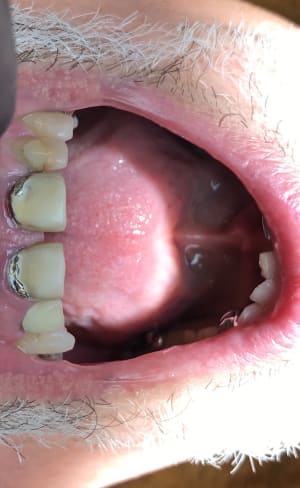

fmc3f4g6br7wgsnveglq.jpg

Voir le message contenant cette image